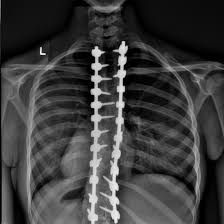

Understanding Scoliosis

Scoliosis Awareness Program